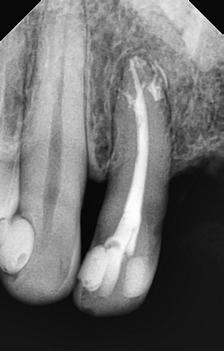

A 10 éves férfi páciens a felső frontfogai késői/nem megvalósuló előtörése miatt kereste fel a rendelőnket. A klinikai és a radiológiai vizsgálat során a jobb felső nagymetszőfog impakcióját észleltük (1. ábra). A fog horizontális tengelyállással és dilacerált gyökérrel rendelkezett. A felső dentális középvonal a fogak vándorlása miatt jelentős mértékben elcsúszott. A bal felső kismetszőfog is rendkívül kedvezőtlen pozícióba került.

Dr. Kazem Dalaie, dr. Samin Ghaffari, dr. Mazir Mir (Irán, Németország) 1. a ábra: Az intraorális felvételen jól látható a jobb felső nagymetszőfog lehetséges impakciójára utaló foghiány.

1. b ábra: A panoráma röntgenfelvételen megfigyelhető a teljes impakcióban lévő jobb felső nagymetszőfog. 1. c ábra: A CBCT felvétel is igazolja a jobb felső nagymetszőfog impakcióját.